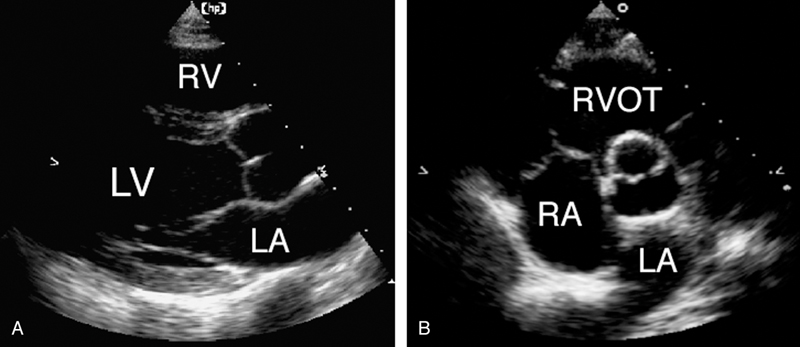

فحوصات تشخيصية لبعض امراض القلب والشرايين التاجية